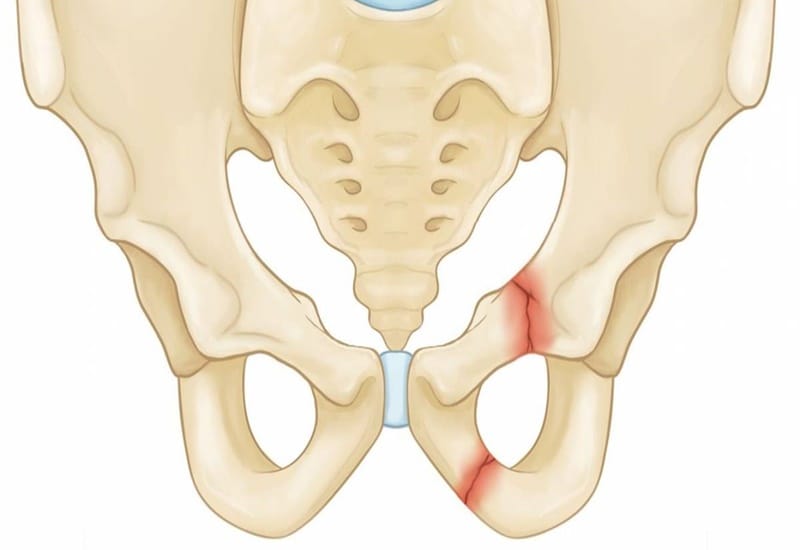

Gãy xương chậu

Khung chậu đóng vai trò nâng đỡ cơ thể và bao bọc nhiều cơ quan quan trọng như bàng quang, niệu đạo, trực tràng. Khi xương chậu bị gãy, đặc biệt là gãy mất vững, người bệnh có thể mất vài lít máu chỉ trong thời gian ngắn và rơi vào sốc chấn thương.

Triệu chứng: đau dữ dội vùng hông – háng, không thể đứng hoặc đi, bầm tím hoặc sưng lớn ở vùng chậu.

Xử lý: cố định chậu bằng đai hoặc tấm vải quấn quanh hông, hạn chế di chuyển, nhanh chóng đưa đến bệnh viện.